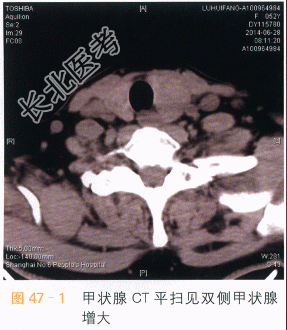

- [材料题] 患者女性,52岁,发现双侧甲状腺结节2年,近期左侧结节增大。体格检查:双侧甲状腺增大,内部扪及多个结节,质韧,活动。实验室和辅助检查TSH5.59IU/ml,T、T正常。超声:双侧甲状腺多个混合性回声结节,形态规则,边缘尚清。左侧结节CDFI未见血流。右侧结节少许血流信号。影像学资料如图所示。